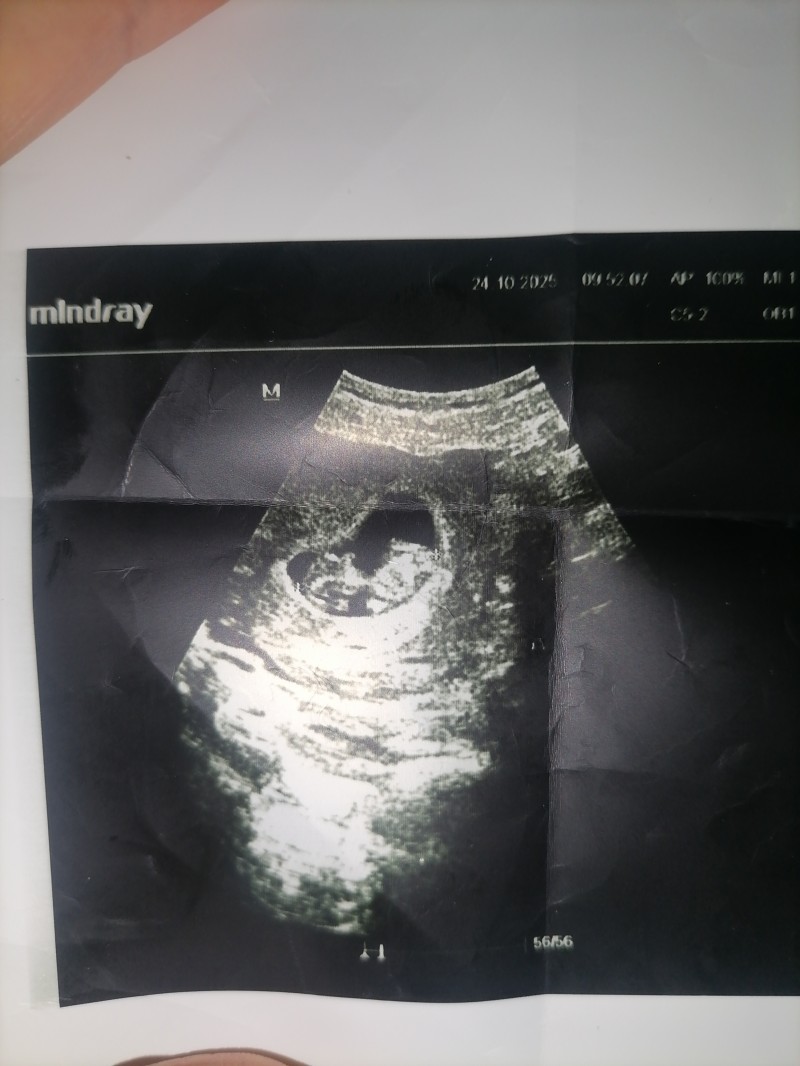

Eğlence amaçlı soruyorum tabiki hemen anlaşılmaz ama tahminleriniz varmı 1 oğlum var

10+6 haftalığım